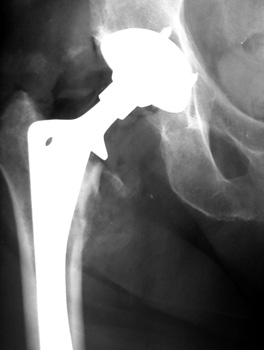

Resection of hardware, flail hip

INFECTION